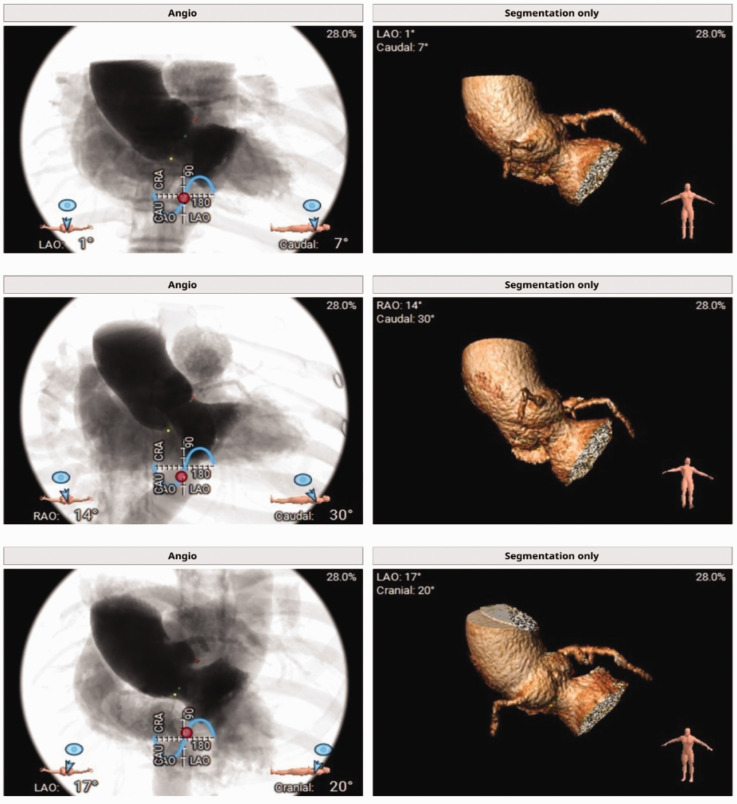

This case report details the successful use of JenaValve for transcatheter aortic valve implantation in a male patient in his early 50s with severe aortic regurgitation. The patient had multiple comorbidities, including chronic kidney disease and heart failure, increasing the risk of surgical intervention. JenaValve, a second-generation device with unique positioning and anchoring mechanisms, was deployed successfully, resulting in immediate improvements in cardiac function without significant regurgitation or paravalvular leakage. This case highlights the potential of transcatheter aortic valve implantation as a viable alternative to surgical aortic valve replacement in patients with severe aortic regurgitation, emphasizing the importance of technological advancements and a multidisciplinary approach in managing complex cardiovascular cases. Long-term follow-up is essential to assess the durability of the implanted valve and the patient's overall prognosis.